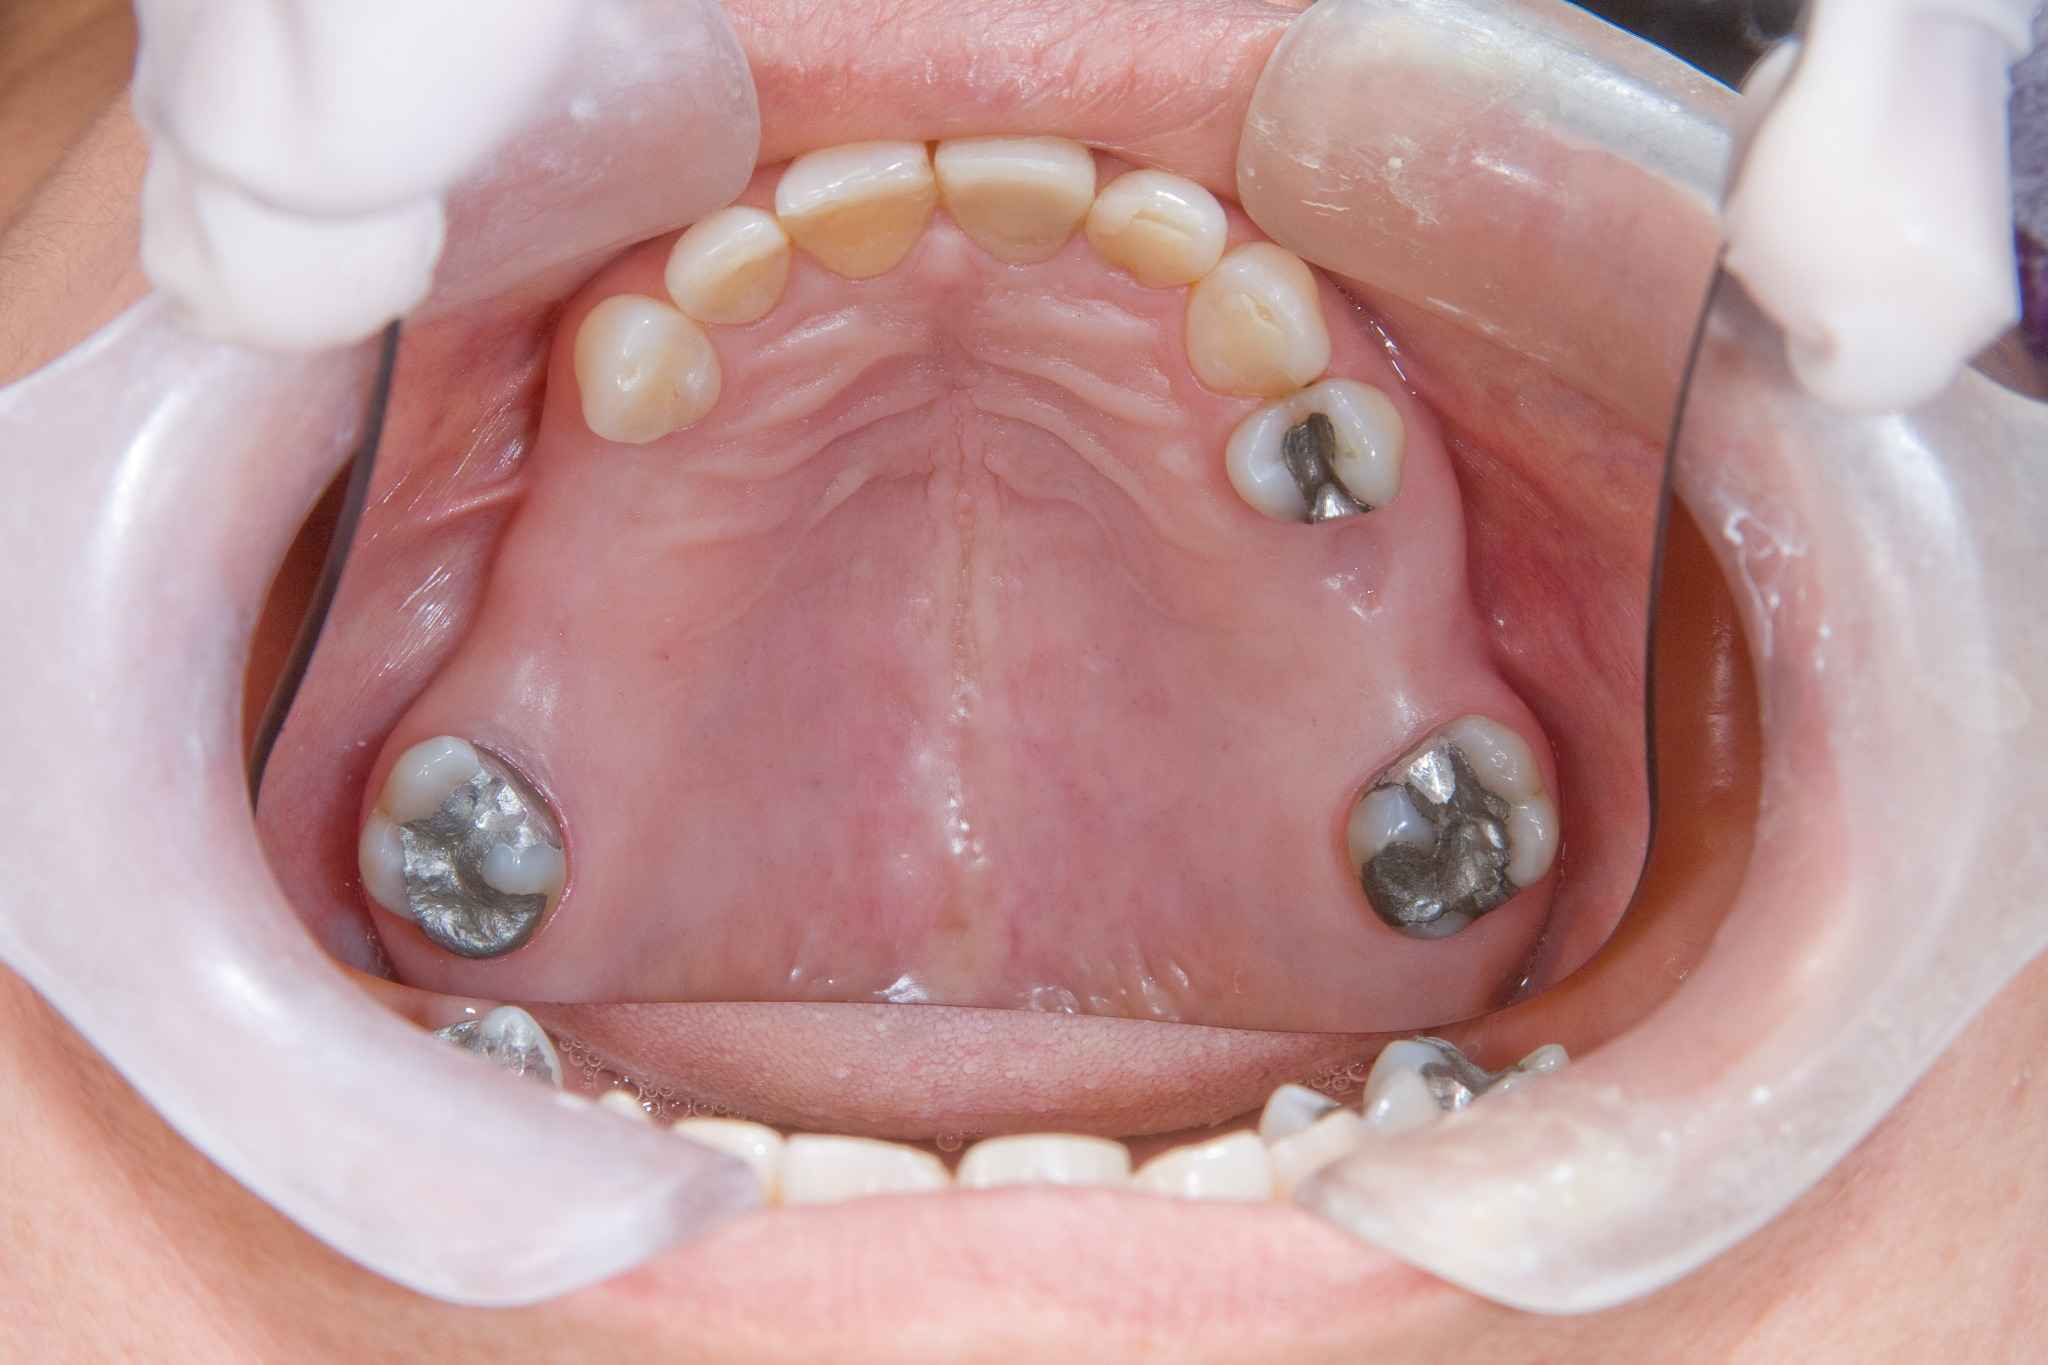

Die All-on-4-Methode richtet sich an Patient:innen, die bereits fast alle oder alle Zähne verloren haben und sich eine festsitzende oder herausnehmbare Prothese wünschen, die viel Komfort bietet. Sie bietet eine ästhetische Lösung für dritte Zähne an einem Tag und meist ohne vorherigen Knochenaufbau.

All-on-4 ist eine innovative Methode zur implantatgestützten Rehabilitation des Kiefers. Sie ermöglicht es, selbst bei sehr geringer Knochenstruktur, Implantate innerhalb eines einzigen Tages einzusetzen, sodass Patient:innen sofort mit provisorischem Zahnersatz versorgt werden. Der Eingriff selbst dauert etwa zwei Stunden.

Anders als bei anderen implantatprothetischen Verfahren müssen die Implantate bei der All-on-4-Methode nach genau definierten Regeln eingesetzt werden. Sie werden im vorderen Kieferbereich gezielt platziert, wo die Knochenqualität und -menge ihre Verankerung und Stabilität ermöglicht. Es werden restliche Zähne gezogen, insofern es keine erhaltungswürdigen Zähne mehr gibt, was meist der Fall ist.